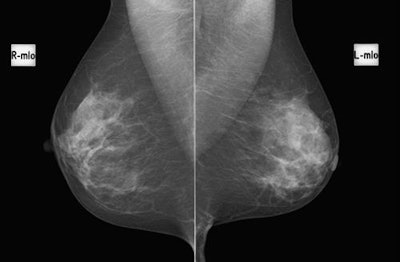

Mammography is a mainstay of breast cancer screening, but criticisms include how the modality overdiagnoses biologically irrelevant cancer and underdiagnoses biologically important cancer, as evidenced by continued breast cancer deaths, according to Kuhl.

The protocol acquires only one precontrast and one postcontrast T1-weighted image set and uses maximum intensity projections (MIP) to fuse the first postcontrast subtracted images into one single high-contrast image. Reading time was less than 3 seconds for interpreting a MIP and shorter than 30 seconds for interpreting the complete study in cases in which there was significant enhancement on the MIPs. The values are competitive with batch reading of screening mammograms and are substantially shorter than the time it takes to review tomosynthesis images.

"The specific advantage of abbreviated breast MRI is that establishing absence of breast cancer -- in other words, reviewing a negative MIP image -- is a simple task that is done within time that is counted in seconds," she wrote. "This is explainable by the fact that MIPs are high-contrast images, whereas with mammographic or tomosynthesis screening, radiologists need to meticulously search low-contrast images for subtle signs of breast cancer."